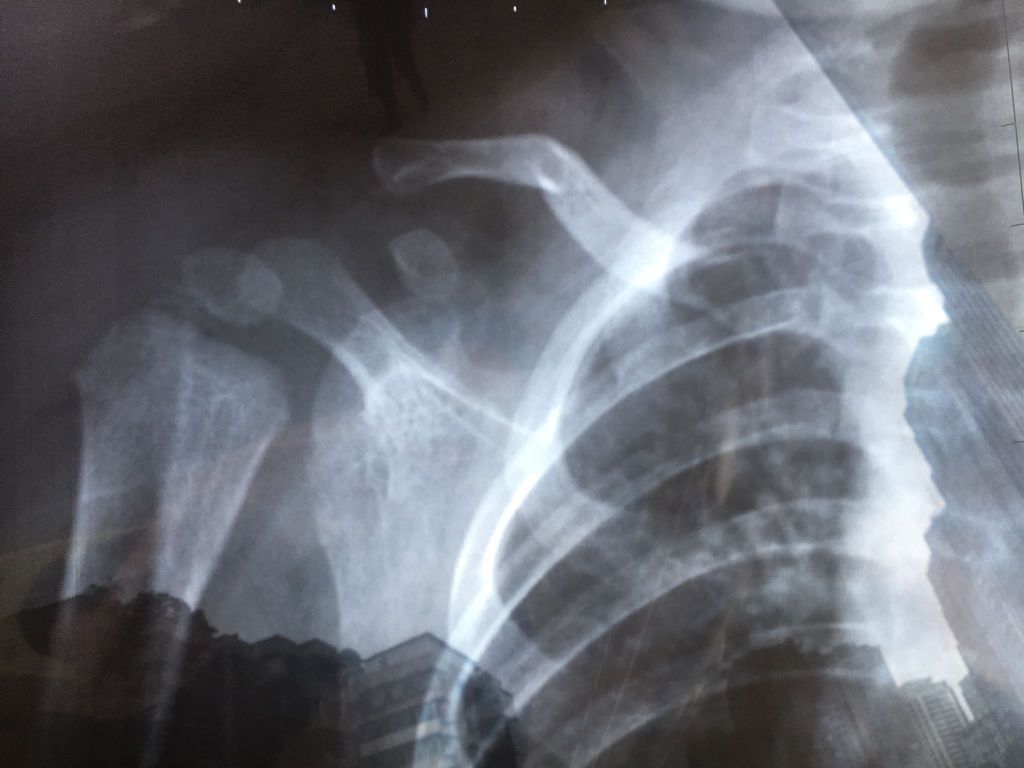

问:十月宝宝从床上摔下右锁骨骨折,医生说自行恢复即可 请问一下回家后要如何护理,有要特别注意的吗? 问:十月宝宝从床上摔下右锁骨骨折,医生说自行恢复即可。请问一下回家后要如何护理,有要特别注意的吗?主要是想问一下对宝宝的活动有没有什么限制 点击展开 匿名用户 2016-10-18 15:45 推荐回答 小孩子惠贸应该很渐瓣沃小,不合适打针吃吧,而且小孩骨骼发育很快,如果不放心,可以去另一个医院核实敲阶,不过你应该把心态放宽 叶寄文_Rihs 2016-10-18 15:53 宝宝知道提示您:回答为网友贡献,仅供参考。 相关问题 昨天晚上我的宝宝从床上掉下来,右锁骨骨折了,有经历过的妈妈没有,希望告诉护理经验,恢复后有后遗症吗 小孩锁骨骨折怎么护理用不用吃点钙片 小儿锁骨骨折如何护理